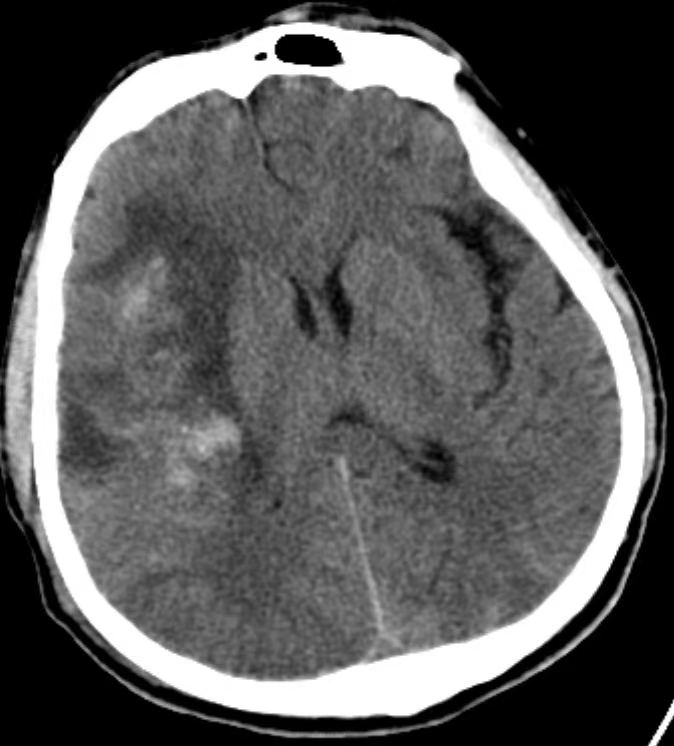

术中CT显示右侧颞叶脑内血肿,出血量约50ml。于床旁行硬通道穿刺引流术,当即抽出陈旧血25ml,用时仅15分钟。术后于ICU治疗,病情逐渐好转,术后3周转康复医院继续治疗,出院时患者意识清楚,左侧肢体不全偏瘫。出院后两周患者已行走自如,专程来院送来了感谢信和锦旗。

术后第1天CT

术后第10天CT